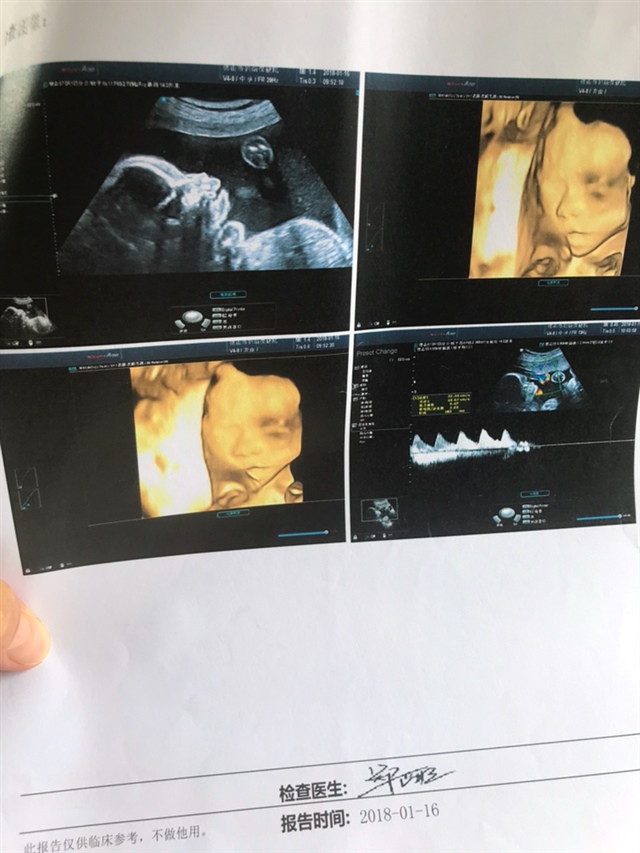

孕28周+0天

孕35周+4天